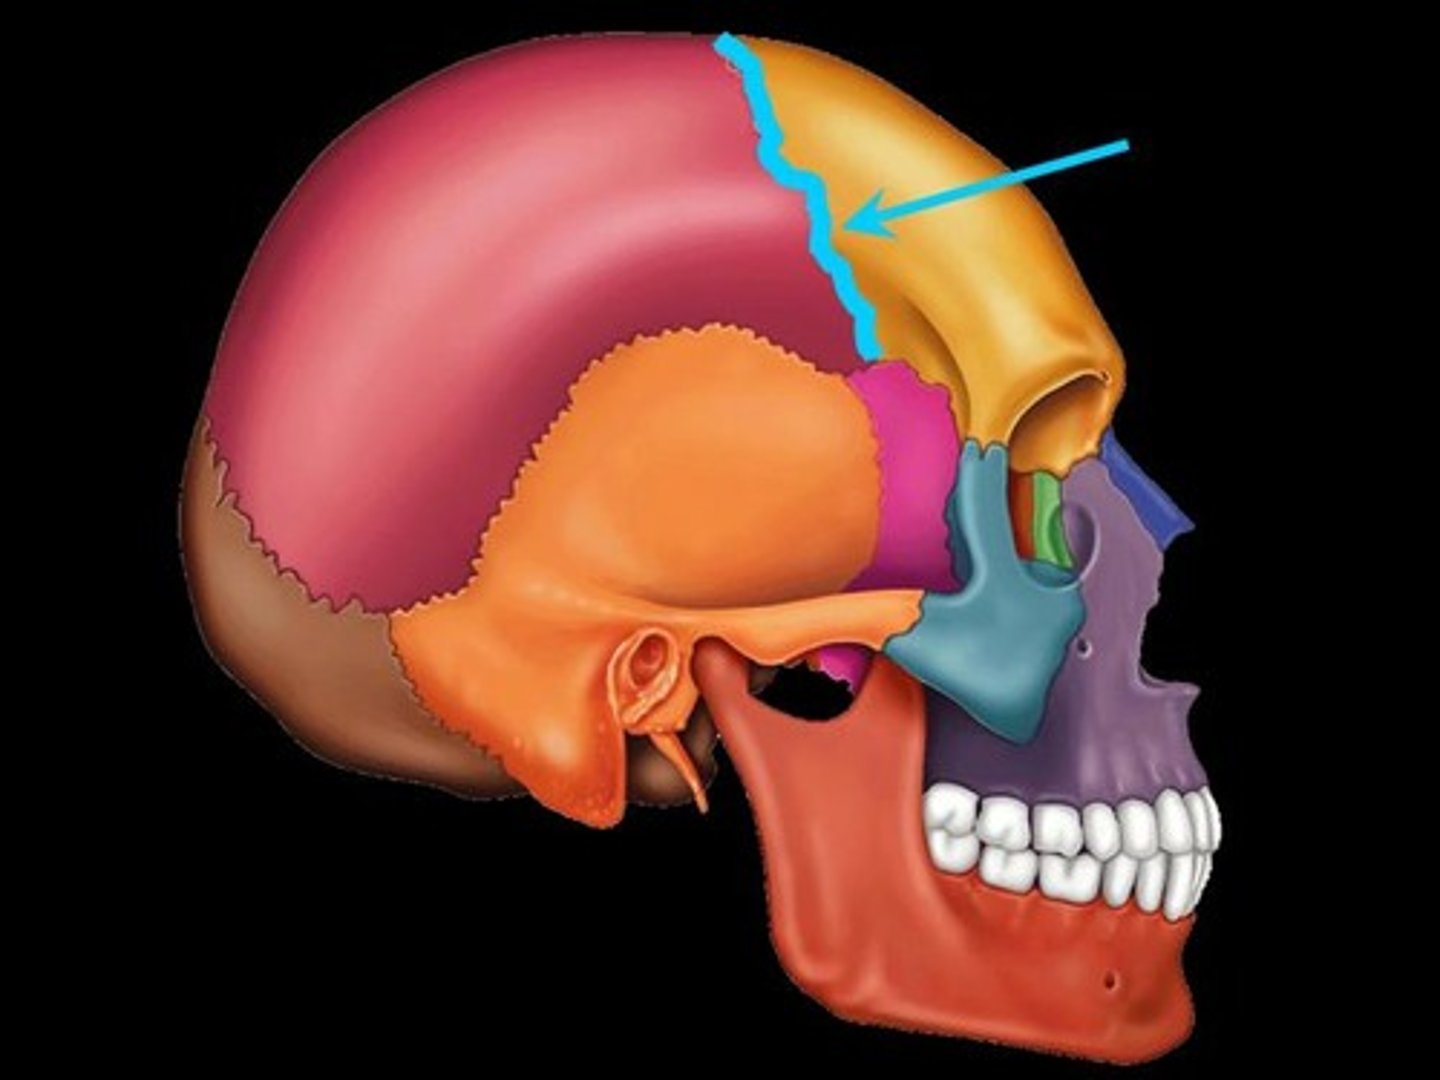

4 Main Sutures of the Skull

- Coronal

Coronal Suture

Suture between the parietal and frontal bones of the skull